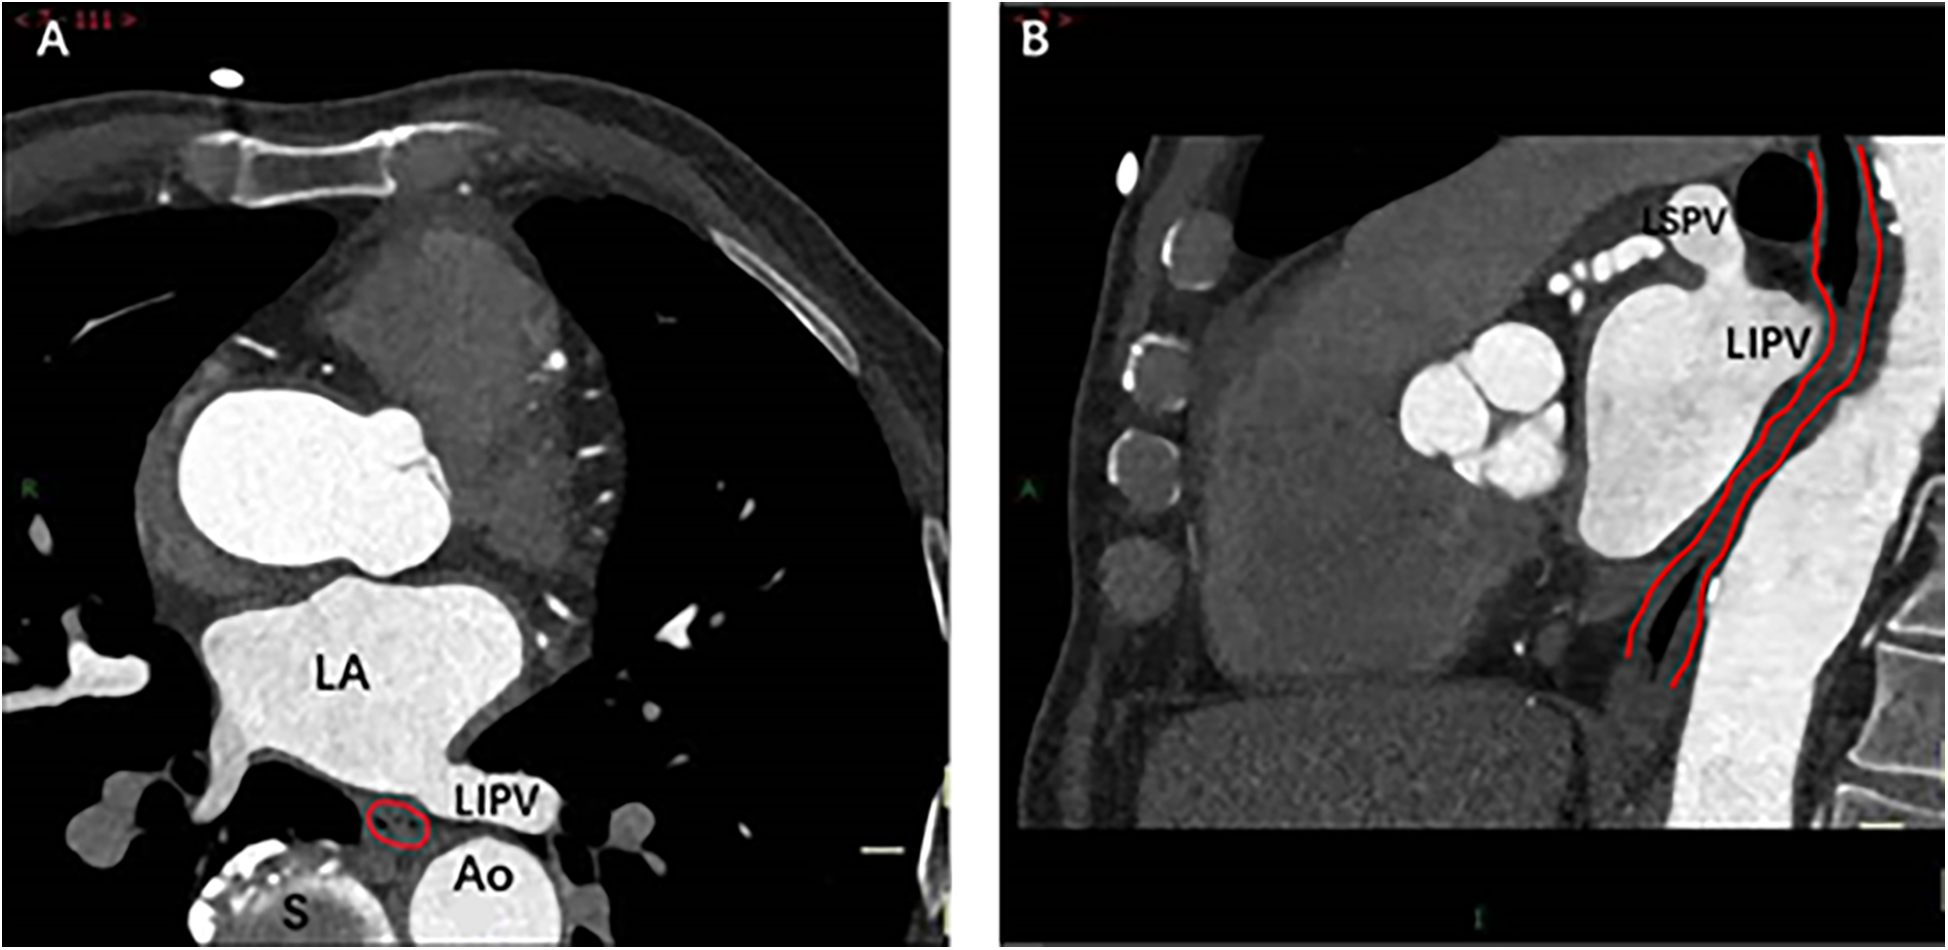

Figure 4

Spatial relationship between MI and esophagus. The cross-sectional (A) and sagittal (B) images show direct contact between the bottom of the left lower pulmonary vein and the esophagus (indicated by red lines). Right image: As the esophagus descends, the spatial distance between it and MI gradually increases. Ao, Aorta; LA, left atrium; LIPV, Left lower pulmonary vein; LSPV, Left superior pulmonary vein; S, spine.